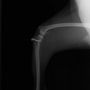

■ 症例20 ポメラニアン 8ヶ月 1.8kg

左右膝蓋骨脱臼 グレードⅢ

2ヶ月前から間欠的跛行が認められ、両膝の膝蓋骨脱臼整復術を行った。

手技は縫工筋及び内側広筋の解放、脛骨粗面の外側転位、滑車ブロック形造溝術、内外側関節包の縫縮を選択し実施した。

右側の膝蓋骨脱臼は上記手技で整復されたものの、左側はそれのみでは膝蓋骨が浮く様子が認められた。その為、PDS縫合糸にて膝蓋靱帯を1糸のみ縫合し、靱帯の縫縮を行った。

膝蓋骨脱臼は膝関節における膝蓋骨の内外側の脱臼と定義されるが、時として単純な内外の脱臼ではなく、膝蓋骨が大きく前方に浮き上がるように脱臼する場合がある。特にトイプードルやポメラニアンといった犬種に多く認められる。

内側脱臼に加えて前方への浮き上がりを矯正する為に、従来より脛骨粗面転移により膝蓋靭帯を外方と下方に引っ張り、固定する方法を選択する。膝蓋骨の前方への浮き上がりが軽度の場合は、従来法ではなく関節包の縫縮で対応していた。しかし、一部の症例で膝蓋骨の動きが悪くなり伸展機構が円滑に機能せずロボット様歩行になるケースがあった。

その為、膝蓋靭帯自体を縫縮する方法を採用した。この方法により、膝関節の伸展機構を妨げず膝蓋骨の軽度の浮きを矯正することが可能となった。

本症例の経過は良好である